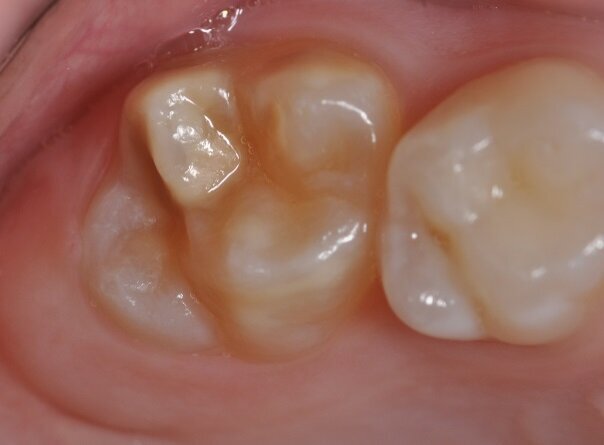

The photograph shows a mild form of MIH. Discoloration indicating the soft enamel can be seen on the occlusal surface of the molar. An important characteristic of such enamel is a hardness reduced by a factor of ten, resulting in likely caries and infraction of the surface under masticatory load. (Photograph: Prof. Norbert Krämer)

With MIH, permanent anterior teeth and, increasingly, second primary molars often present with defective structures. Clinically, the severity may vary greatly, from a single cusp to the entire surface of the tooth. The mild form of MIH appears as white-yellowish or yellow-brown irregular opacities of the occlusal surface or cusps. The severe form exhibits chipped or abraded enamel and dentine of varying degrees. The affected patients suffer from pain when drinking, eating and brushing their teeth.